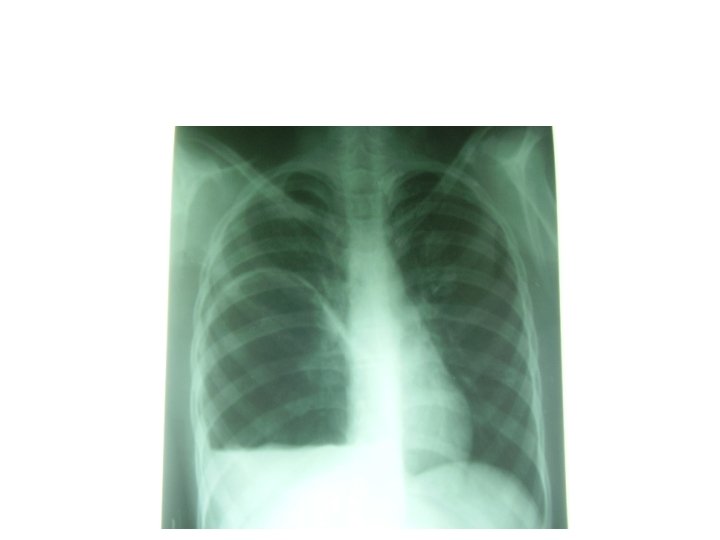

Kyste hydatique du poumon • Evolution radio-clinique 06 stades successifs: 1) Kyste sain. Asymptomatique de découverte fortuite (stade exclusivement radiologique)= opacité ronde, nettement limitée, en « boulet de canon » , dans un parenchyme sain, profil, opacité ovalaire « en ballon de rugby » , signe de NEMENOFF en radioscopie